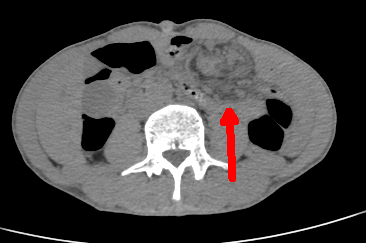

▲ 术前腹部CT可见小肠“旋涡”征,提示肠扭转

一年前患者郭师傅曾做过一次“胃大部切除”手术,近半年来腹痛间断性发作。近日,他的腹痛再次持续加重,并伴有淡绿色胃液呕吐物。入住郑州大学五附院消化内科一病区后,黄煌博士为其详细查体,发现腹部呈不对称性隆起,考虑不排除肠扭转可能。通过急查血常规、CT检查证实判断后立即转入胃肠甲状腺外科进一步治疗。

SBV可以发病于各个年龄阶段,青年SBV发病较老年患者更为典型,早期症状明显,患者往往有腹痛难以忍受的症状,大部分SBV发病于某种病理变化比如手术后局部的粘连、肠系膜肿瘤、系膜过长等。SBV可有多种不同的表现,较为复杂,CT对于诊断小肠扭转具有更直接明确的参考价值。